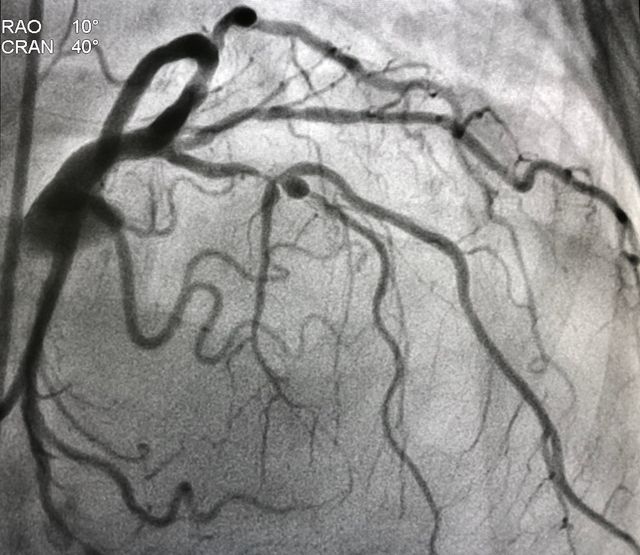

Navigate through our brain, spine and neurovascular pages to learn more about specific conditions and the innovative neurosurgery technology we use to treat them. Each page provides you with detailed information on tumors, strokes, spinal stenosis and more, with helpful links that can better inform you and your loved ones.

IGEA Brain, Spine, Pain & Orthopedics is a world-class center of neurosurgical excellence that delivers information for each field of practice to patients in New Jersey and across the nation. Select any category below to learn more about your condition and the leading edge surgical systems we use to help guide you into a state of health and well-being.